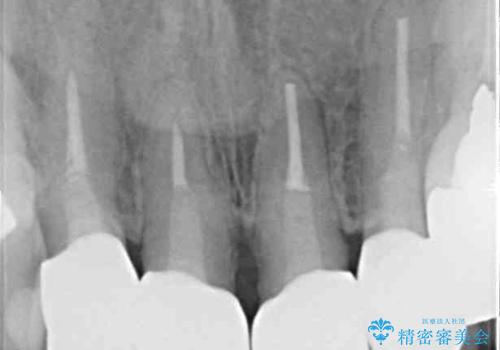

また、裏打ちに主に銀を用いた金属材料を使用するため、金属自体が黒くなったり、イオンとなり溶け出したりして、歯肉ラインが黒くなってしまうことがあります。

金属の土台を歯の色に近いものへと変更した上で、オールセラミッククラウンにて補綴することとしました。